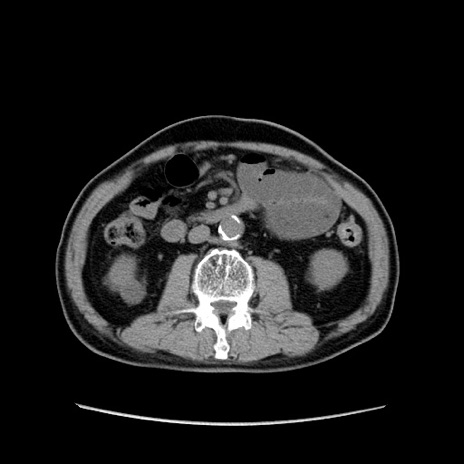

症例24(横断像)

【症例】80歳代男性

【主訴】左側腹部痛、嘔吐

【現病歴】本日早朝より左腹部に痛みあり。昼頃嘔吐認めたため、救急要請。

【既往歴】直腸癌(Mile手術)、胆摘

【身体所見】意識清明、BT 35.9℃、BP 221/93mmHg、SpO2 97%(RA) 、腹部:左ストーマ周囲に限局性の腹部膨隆あり。 膨隆部自発痛・圧痛あり・軟。

【データ】WBC 7700、CRP 0.09